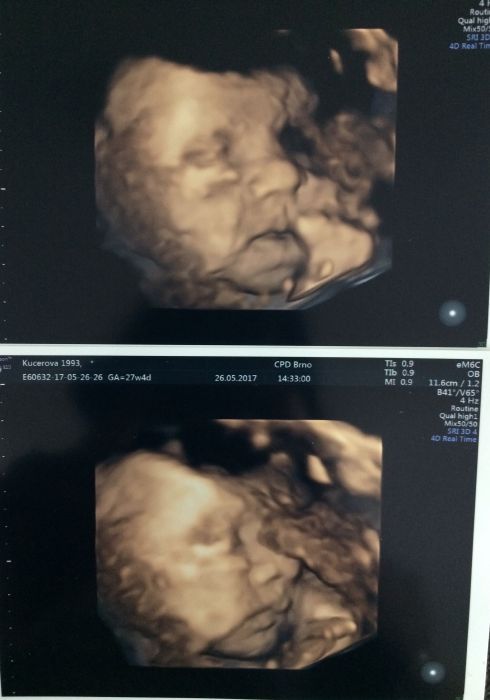

Ahoj holky, tak ja musim zaklepat, ze u me je stale vse v naprostem poradku :-). Tehotenskou cukrovku nemam a nemoci(krome trech oparu, ktere se mi od zacatku postupne udelaly) se mi take vyhybaji. Co se tyce vahy, tak ta narusta postupne a momentalne jsem na 7 kilech :-). Konecne me nikdo nepodezira, ze jsem anorekticka :-D. Asi budu byvat tehotna casteji :-P. Mame za sebou i 3D, ale ta nase prdola teda moc nespolupracovala. Takze po dvou navstevach mame aspon dve fotky a stoprocentni potvrzeni, ze to bude holka :-). Asi nam chtela setrit penezenku :D. Dnes mam za sebou kontrolu, mala uz je krasne hlavickou dolu a ma kilecko. Jinak k dnesnimu vstupu do osmeho mesice(beru to podle tech lunarnich) mam uz vybavicku pro malou skoro kompletni. Na zaver si nechavam jen kosmetiku, chuvicku a uvazuji o monitoru dechu. No, a musim teda rict, ze prvni jizdy kocarkem se uz nemuzu dockat :-D. Koupili jsme kocarek presne podle mych snu :-). Strasne vam vsem zavidim, ze se vam ti prckove narodi na zacatku srpna- ja si musim pockat az skoro na konec :-/. Mejte se krasne a prezivejte v poklidu ty paraky ;-).